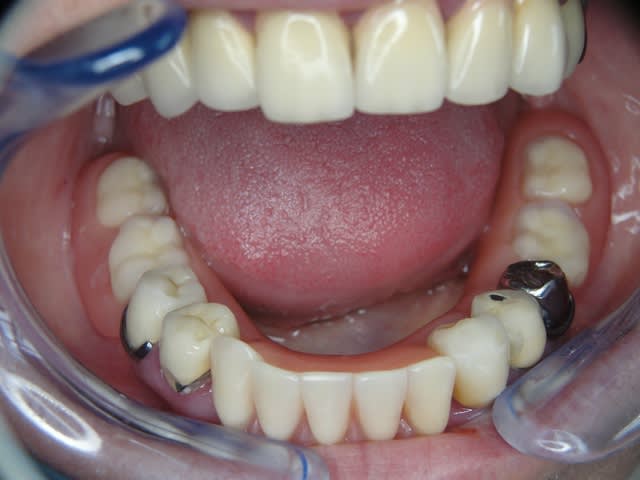

Maintenant concernant la demande de scans : je poste ce cas, une patiente vient me voir avec son scan car elle a consulté d'autres "spécialistes" et on lui refuse la pose d'implant secteur 4 où alors avec greffe préalable..Ca se discute..pas de temps à perdre je sais faire autrement..

Avec la chir trans gingivale technique MIMI ( Oui..un post sur la technique bientôt ..) j'ai pu placer deux 3,5/8mm..aurai je eu le meme résultat avec un lambeau..j'en doute..Les couronnes sont en titane. Recul clinique 2 ans ras. Simple efficace rapide moins onéreux satisfaisant pour le praticien et la patiente..